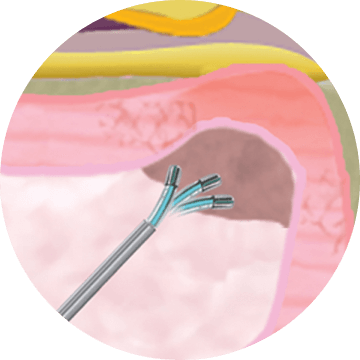

Чрескожный заднелатеральный

доступ через канюлю диаметром

3,0 миллиметра

Стандартная механическая

нуклеотомия с использованием

миниатюрных кусачек

Управляемый, гнущийся электрод — точная локализация радиочастотного воздействия на пульпозное ядро и фиброзное кольцо